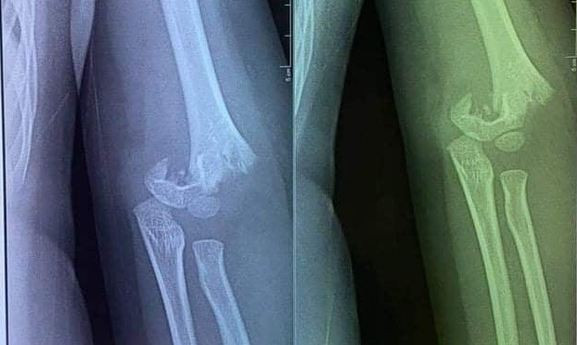

| Hình ảnh chụp phần xương cánh tay của cháu bé. |